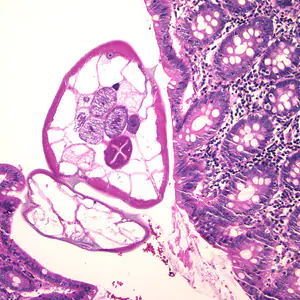

A 27-year-old woman who had been working in Laos, Thailand, and Vietnam for one and a half years was visiting relatives in the U.S. While she was in the U.S., she visited a physician for recurring abdominal discomfort, bloating, and frequent bowel movements that she had experienced over the last two months.